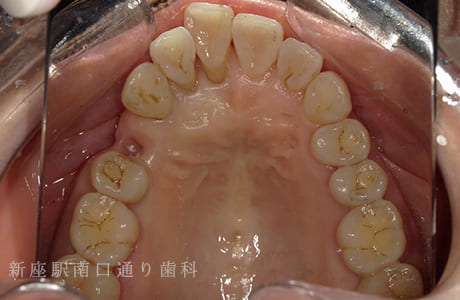

CASE.02

左上のフルジルコニアブリッジで

修復した症例

- 主訴

- 歯がないところを治したい

- 治療法

- 左上にフルジルコニアブリッジで修復

- 治療期間

- 1ヶ月半

- 費用

- ¥240,000(税込)

【リスク・副作用】

過度の咬合や衝撃で割れることがあります。治療直後は歯や歯茎に一時的な違和感や痛みが出ることがあります。